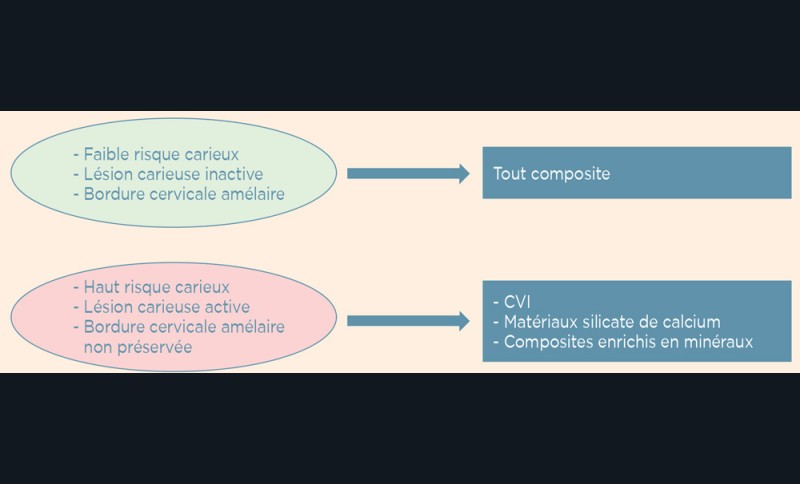

Le choix de la prise en charge de la lésion carieuse dépend de trois critères fondamentaux : l’activité de la lésion carieuse (active ou arrêtée), la présence ou non de cavitation et l’accessibilité (site proximal difficile d’accès) (fig. 3).

- soit de façon invasive a minima. Cette économie tissulaire peut se faire notamment avec l’utilisation de fraises adaptées et minimalement invasives (fig. 4).

• Traitement invasif a minima : il concerne les lésions carieuses cavitaires ou non avec atteinte dentinaire (à partir du 1/3 moyen dentinaire), soit ICDAS 3 à 6. Dans ce cas, la priorité est de préserver la dent d’une effraction pulpaire éventuelle (recommandations de l’ESE) [4]. C’est pourquoi, lors du traitement de lésions carieuses profondes (ICDAS 4 à 6), il faut dans tous les cas réaliser une éviction sélective, réaliser une préparation a minima (favoriser les préparations de type fente (« slot ») ou tunnel lorsque l’indication se pose) et utiliser un matériau de restauration de choix, soit composite, soit un ciment verre ionomère (CVI), soit des matériaux à base de silicate de calcium ou encore les nouveaux composites enrichis en minéraux (fig. 7 à 9). Ces préparations a minima peuvent être réalisées avec des fraises de petits diamètres (fig. 10 et 11).